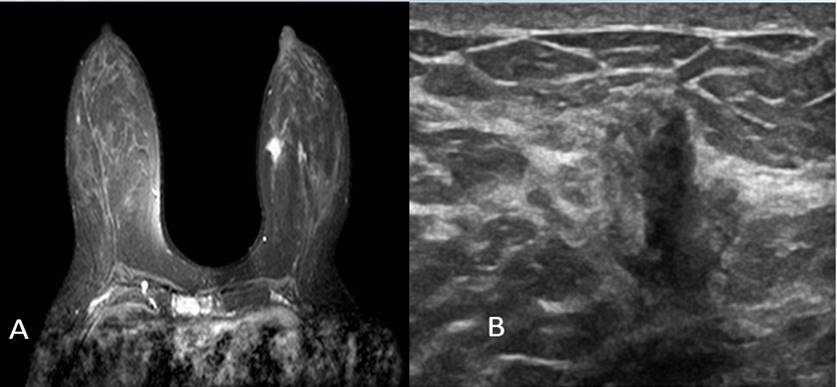

Figura 3. A. Reconstrucción MIP Proyección de máxima intensidad. (corte axial imagen posterior a administración de gadolinio). Se observa captación nodular de morfología irregular de márgenes espiculados . B. Second look ecográfico. BIRADS 5

En la ecografía mamaria. BIRADS0, adenopatía axilar derecha a nivel I. informa de mamografía indica tejido mamario heterogéneamente denso ACR C. La densidad mamaria no permite la identificación de lesiones nodulares, ni lesiones no nodulares. Se realiza resonancia magnética de mama, evidenciando lesión estelar de 17x15 mm localizada en la unión de los cuadrantes internos de mama izquierda. Por lo cual se realiza second look ecográfico y se biopsia lesión ecoguiada de lesión mamaria izquierda y además aspiración de lesión ganglionar derecha. Con reporte de carcinoma invasor lobulillar infiltrante de mama positivo al receptor de estrógeno, positivo al receptor de progesterona, Her 2 negativo, cadherina negativa, k-67 expresión nuclear en el 15 % de las células. Paciente en contexto de Cáncer de mama, premenopáusica, se realizará supresión ovárica para posteriormente tratamiento hormonal.

La búsqueda del tumor primario clásicamente se realiza a través de la mamografía, sin embargo, la sensibilidad del método, en estos casos varía entre 0 % y 56 %, según lo que reporta la literatura,(10,11) de ahí que varios estudios actuales han demostrado el potencial de la resonancia nuclear magnética (RNM) para detectar lesiones ocultas, con cifras de sensibilidad del método de hasta 85 % a 100 %.(10,12,13)